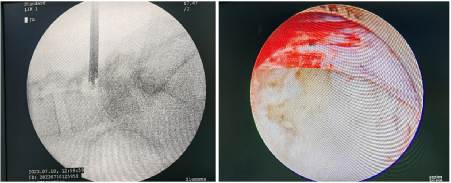

Alat teropong tulang belakang dihubungkan melalui kabel optik ke sumber cahaya dan pengolah data, kemudian ditampilkan ke layar monitor sehingga didapatkan gambar struktur dalam tulang belakang, yang diperbesar dan jelas.  Prosedur dipandu dengan alat ronsen (fluoroscopy) sehingga prosedur dapat dilakukan lebih akurat dan tepat.

Gambar : Prosedur Spinescopy (PELD Interlaminar) Gambar hasil teropong sendi: Kiri						: hasil gambar fluoroscopy       Kanan	: hasil gambar monitor teropong